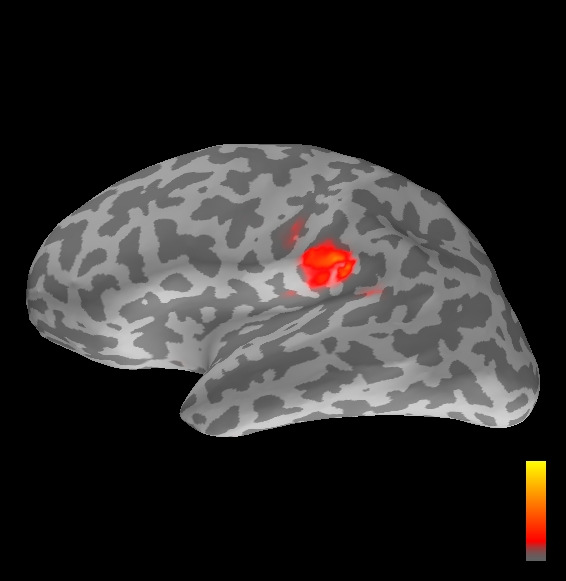

5.2 Results

We applied the ASMC sampler to MEG topographies taken from the above recordings by selecting specific time points according to the previous analysis; the parameter values in the algorithm were the same as those used for the analysis of synthetic data, with the only exception of the noise standard deviation , here estimated from the pre–stimulus interval. In order to validate the results of the ASMC, we also computed source estimates using three other methods: a PF, that approximates the posterior distribution for the current dipoles conditioned on the data up to the selected time point; dSPM, which is based on a distributed source model with an –prior, and consists in normalizing the Tikhonov regularized solution by the noise standard deviation; and sLORETA, which is similar to dSPM but is claimed to have a smaller localization bias. Figure 4 shows the results at , and ms after the stimulus onset. The results are visualized on a computer representation of the brain obtained by “inflating” the cortical surface: gray levels contain the anatomical information, light gray representing gyri and dark gray representing sulci; the activity estimate is coded in color scale, increasing from red to yellow. Importantly, this visualization allows activity in the sulci to be clearly visible; on the other hand, since neighbouring volumes may be moved apart by the inflation process, distinct activity regions are often due to underlying volumetric masses that are very close to each other.

Before describing the results, let us comment on the qualitative difference between the images produced by the ASMC sampler and the PF, on the one hand, and those produced by dSPM and sLORETA, on the other. First of all, we point out that all the quantities shown in the images of Fig. 4 are somehow related to the probability of activation at specific locations. Indeed, for both the ASMC and the PF we plot the approximation of the intensity measure (3.8); for any single grid point, this value can be interpreted as the probability of a dipole being at that location, while it integrates, over a given volume , to the mean number of dipoles within . As for dSPM, the represented quantity is a statistical value that is –distributed under the null–hypothesis of zero activity; as a direct consequence, it also yields a probability of activation, which is however not constrained to be dipolar. Similar considerations apply to sLORETA, although with a different statistical distribution. Importantly, the representation of the results is clearly affected by the setting of the visualization threshold. Owing to the explained differences between the methods, it seems reasonable to use a different value for each method. At the same time, since the plotted quantity is a probability of activation, it seems right to use the same thresholding for different time points. In this connection, the thresholds in Fig. 4 have been chosen by hand following the guidelines just outlined.

Using the same thresholding and parameters at different time points makes the four methods respond differently to the diverse intensities of the different sources. Whenever a stronger source is active, both sLORETA and dSPM will tend to produce widespread estimates, while weaker sources will be represented as small active areas. The behaviour of the ASMC and of the PF is the opposite: a stronger signal will lead to a precise localization of a dipolar source, and then to a focal marginal distribution for the location; a weaker signal will translate to higher uncertainty on the source position, and therefore a more widespread posterior map.

At ms, the ASMC localizes again two sources: a stronger one in the right primary somatosensory cortex, and a weaker one in the left posterior frontal area. Both of them seem to be compatible, for timing and location, with the results in Mauguiere et al. (1997), the left dipole corresponding to the Frontal Ipsi source. Once again, the other three methods only recover the stronger source.